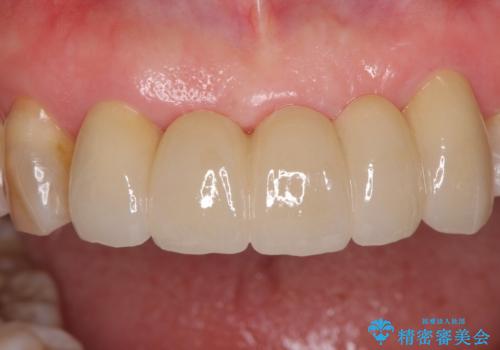

装着されていたブリッジは、支台となっている歯と欠損している歯で色が大きく異なっていましたが、オールセラミックとしたことで、全体的に色調の整った仕上がりとなりました。

歯肉ラインがきれいに整い、患者様には大変満足していただきました。